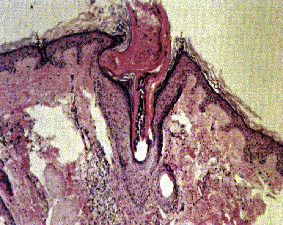

Immagine istopatologica di Lupus Eritematoso Discoide